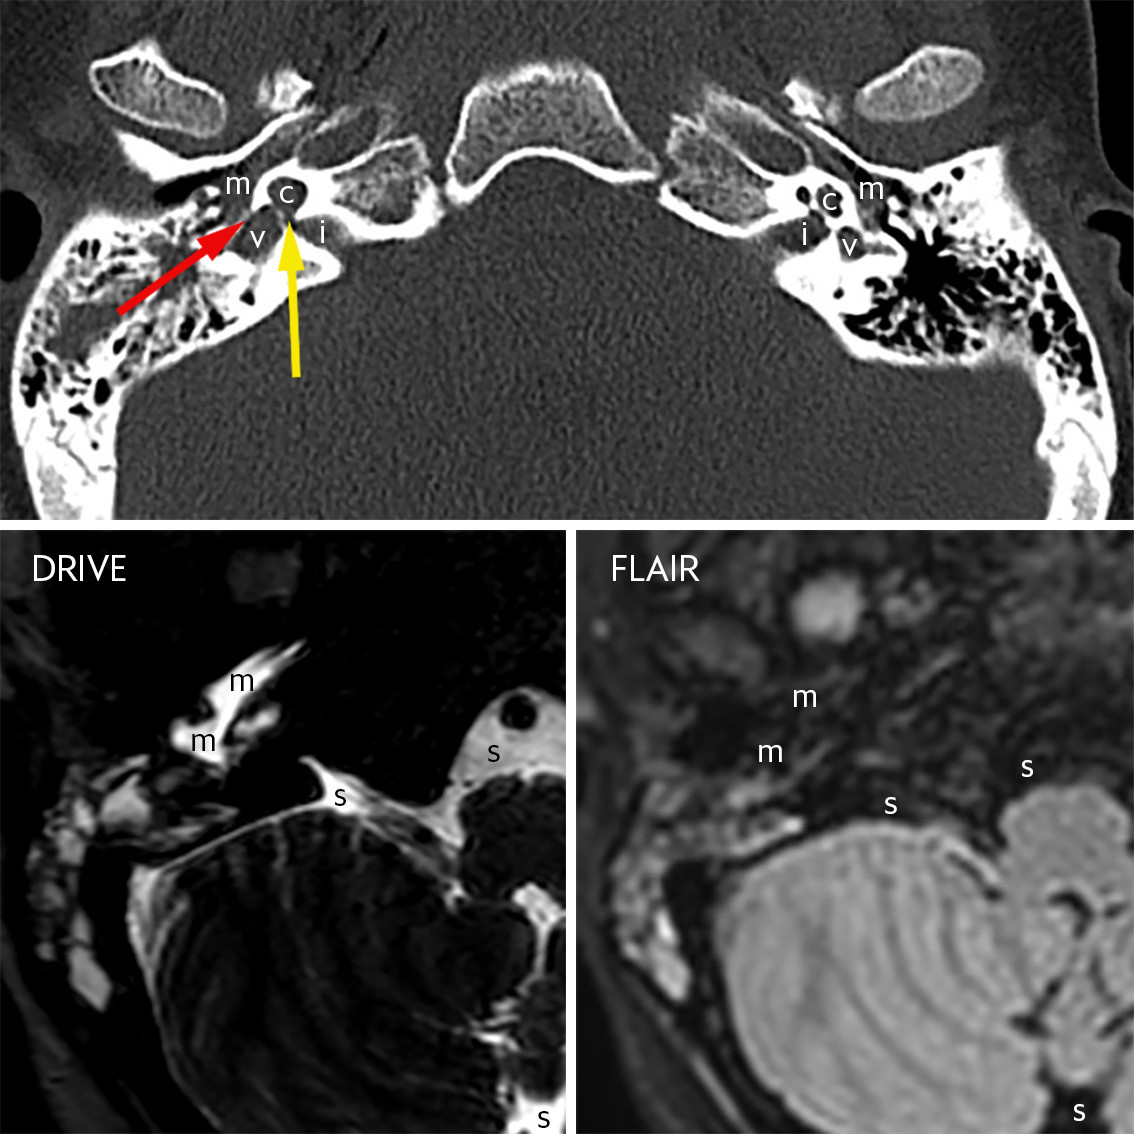

Det øverste bildet er et utsnitt fra en standard CT caput med volumopptak, her vist med benalgoritme og benvindu i nivå med indre øre. Indikasjonen var et kritisk sykt barn med redusert bevissthet. Mellomøre (m), cochlea (c), vestibulum (v) og indre øregang (i) er markert bilateralt. Indre øre på venstre side er normalt. I indre øre på høyre side er det en medfødt malformasjon. Cochlea har normal størrelse, men fremstår cystisk og mangler intern arkitektur. Det er en bred åpning (gul pil) mellom basis av cochlea og indre øregang. Vestibulum er forstørret, men kan differensieres fra cochlea.

Malformasjonen er forenlig med incomplete partition type 1, tidligere kalt cystisk kokleovestibulær malformasjon (1). Ved denne malformasjonen har de fleste et uttalt nevrogent hørselstap ipsilateralt. Hos noen vil det også foreligge lekkasje av cerebrospinalvæske fra indre øregang til mellomøret via en fistel gjennom indre øre. På bildet ses innhold i høyre mellomøre lateralt for det ovale vindu (rød pil). Dette er et uspesifikt funn, men det kan være for eksempel cerebrospinalvæske og/eller infeksjon.

De to nederste bildene er fra en MR-undersøkelse tatt ti dager etter CT. Pasienten ble i mellomtiden behandlet for pneumokokkmeningitt. Det er utsnitt av to sekvenser, 3D-T2-DRIVE og fettsupprimert 3D-T2-FLAIR, i nivå med nedre del av mellomøret. Bare høyre side er vist. Det er innhold i mellomøret (m) som har svært høyt signal på DRIVE og supprimert signal på FLAIR. Dette er samme signalmønster som man ser i cerebrospinalvæsken i subaraknoidalrommet (s) omkring hjernestammen og lillehjernen. Dette er en indikasjon på at det foreligger cerebrospinalvæske i mellomøret og er et indirekte tegn på at det kan foreligge en cerebrospinalvæskefistel (2). Denne kan verifiseres ved positiv test på beta-2-transferrin, forutsatt at det kan samles nok væske til analyse (2). En cerebrospinalvæskefistel til mellomøret medfører risiko for residiverende bakteriell meningitt og kan behandles med kirurgisk lukking (1).